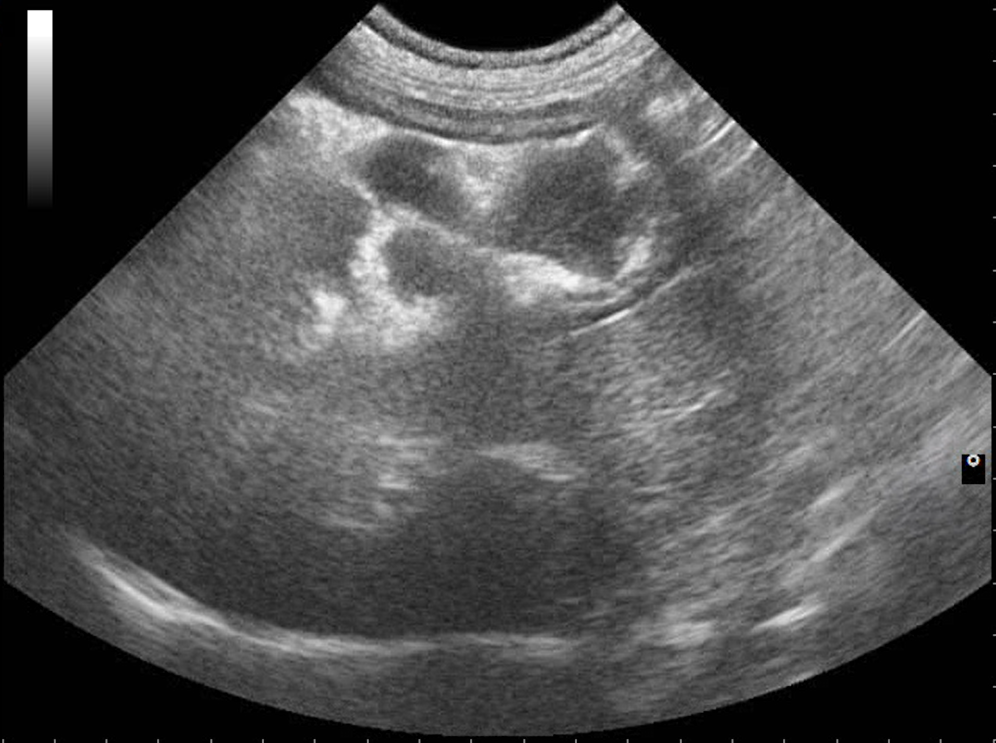

Webinář zaměřen na klinicky orientovanou sonografii gastrointestinálního traktu, se zaměřením na patologické nálezy, které mají přímý dopad na další diagnostický a terapeutický postup. Čeká na vás více než 50 komentovaných videosmyček z reálných klinických případů.